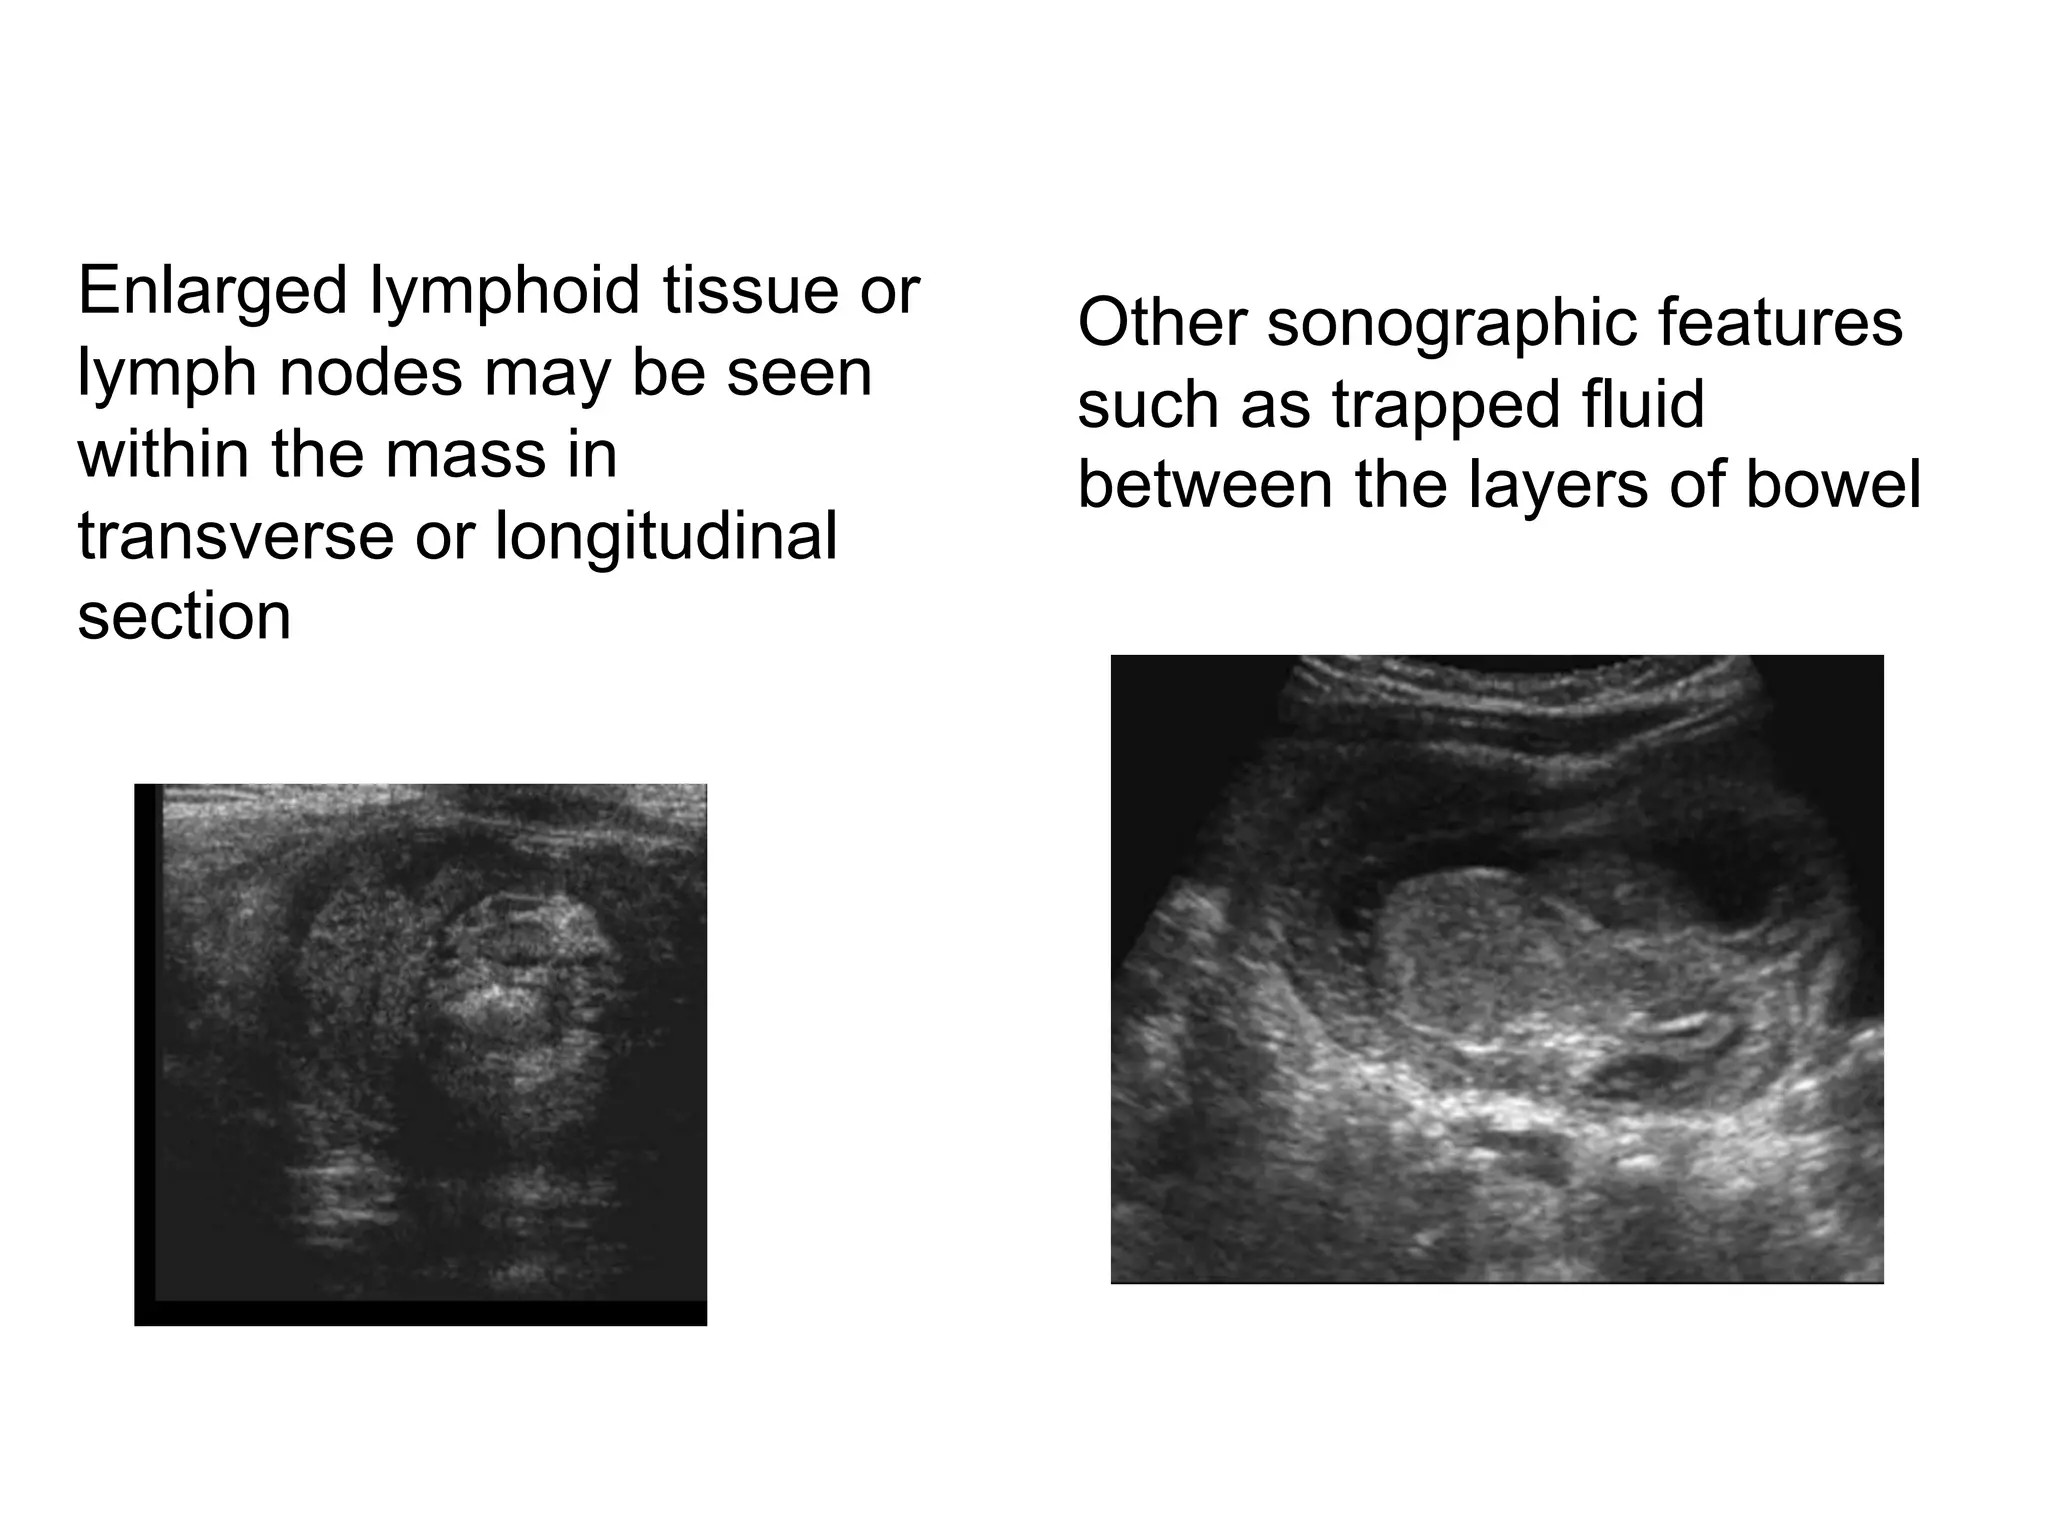

Enlarged lymphoid tissue or

lymph nodes may be seen

within the mass in

transverse or longitudinal

section

Other sonographic features

such as trapped fluid

between the layers of bowel